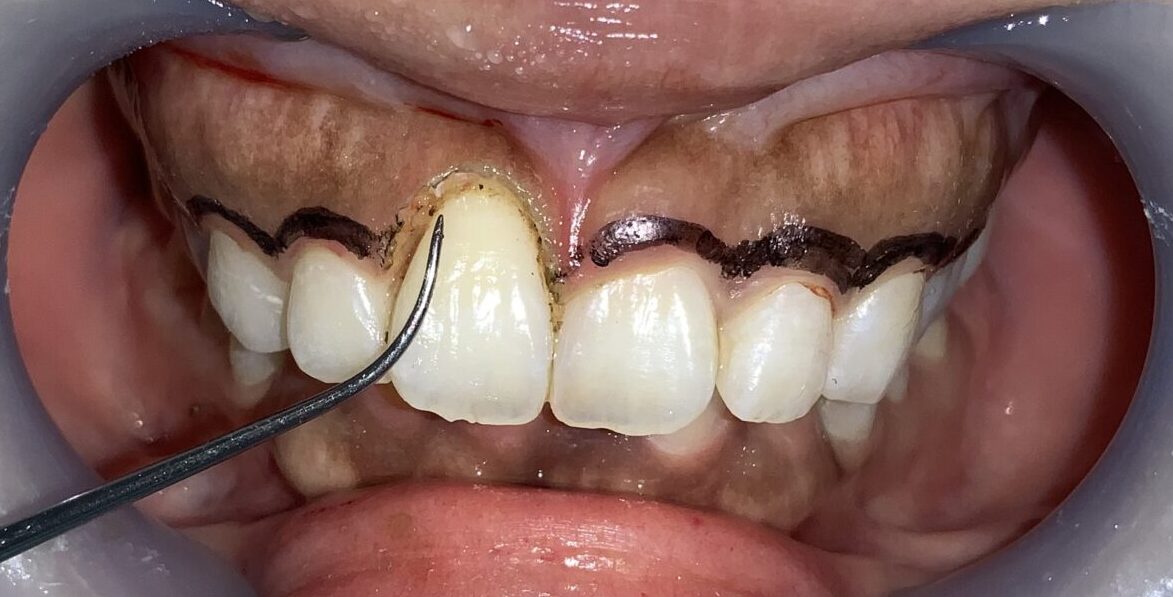

検査結果から、歯ぐきの切除範囲をマーキングして、もう一度検査データと切除範囲の間違いがないかを確認します。

切除範囲の設定は完璧です。

まずは1本だけ歯ぐきの整形を行なって、患者様に確認をして頂きます。

歯ぐきの面積が小さくなり、歯が大きくなり、歯ぐきの形が整っています。